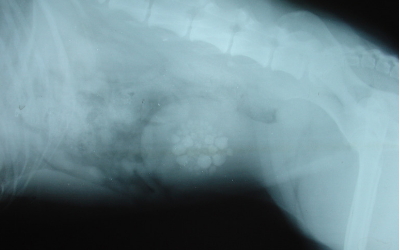

Unfortunately, many cystine stones are radiolucent, meaning they are not visible on X-rays (radiographs). Your veterinarian may need to perform other imaging, such as a bladder ultrasound or a contrast radiographic study, a specialized technique that uses dye to outline the stones in the bladder. If your veterinarian suspects that your dog has cystine bladder stones based on breed, clinical signs, and results of a urinalysis, one or both of these specialized imaging techniques may be recommended.

The only way to be certain that a particular bladder stone is a cystine bladder stone is to have it analyzed at a veterinary diagnostic laboratory. In some cases, your veterinarian may make a presumptive diagnosis about the type of stone based on the findings on imaging studies and results of a urinalysis. For example, if your dog is one of the breeds predisposed to this type of stone, if ultrasound or contrast X-rays show that there are one or more stones present in the bladder, and if the results of the urinalysis show the presence numerous cystine crystals, your veterinarian may make a presumptive diagnosis of cystine bladder stones and start treatment accordingly.